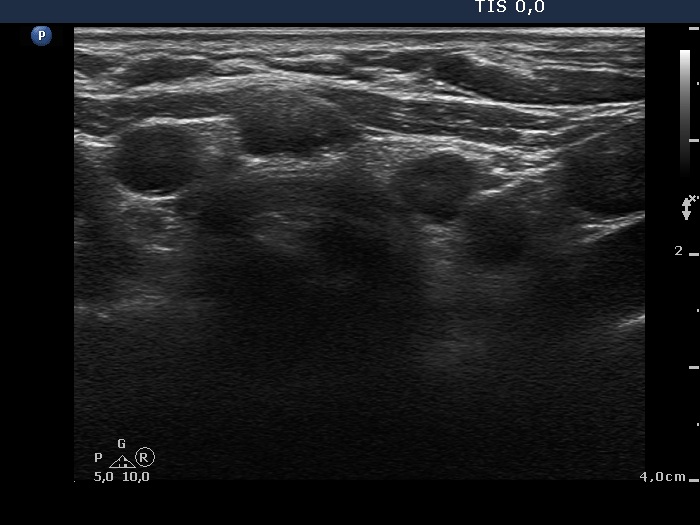

Ultrasound. Connective tissue replaced the thyroid parenchyma in both thyroid beds. There were tiny hypoechoic areas in the right thyroid bed. Two larger hypoechoic lesions were found, one in the isthmus and the other in the left thyroid bed. The latter presented vascularity.

Comment. The presentations of the hypoechoic lesion in all three sites were the same, they differed only in their size. Naturally, the two larger in the isthmus and in the left thyroid bed could cause and did cause concern. Especially that in the left lobe due to its intralesional vascularity. The larger lesions can correspond to small muscle fibers, remnant of the regenerative provess after the surgery but even damaged, non-viable thyroid tissue. Taking the thyroglobulin level into account, the risk of thyroid cancer is minimal but not zero.